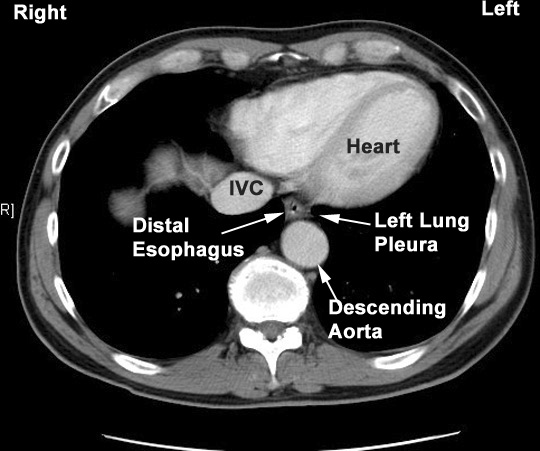

Heart Distal

- Anterior

- Trachea

- Left main stem bronchus

- Pericardium

- behind and to the right of aortic

arch

- Posterior

- Vertebral column

- Hemiazygous vein

- right aortic intercostal arteries

- aorta near diaphragm

- Right

- right pleura

- azygous vein

- Left

- aortic arch

- left subclavian artery

- left pleura

- descending aorta